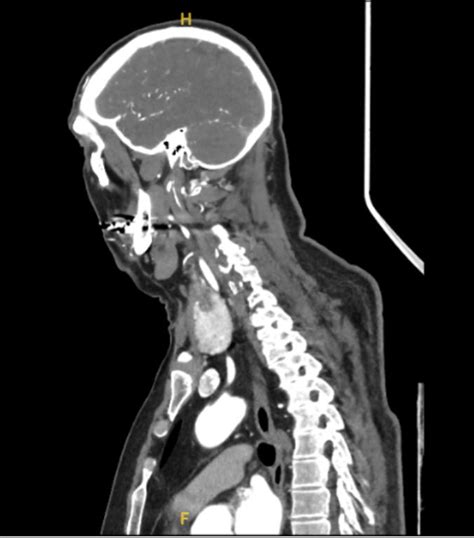

A professional can help determine if physical therapy, medication, or imaging (like an X-ray or MRI) is necessary to diagnose the underlying cause of your neck pain left side, such as a herniated disk or severe muscle imbalance.